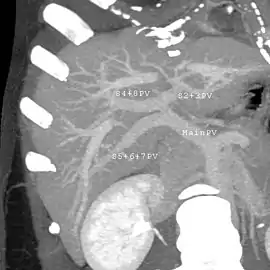

Axial CT image showing anomalous hepatic veins coursing on the liver's subcapsular anterior surface[66]

Maximum intensity projection (MIP) CT image as viewed anteriorly showing the anomalous hepatic veins coursing on the anterior surface of the liver

Lateral MIP view in the same patient as previous image

A CT scan in which the liver and portal vein are shown